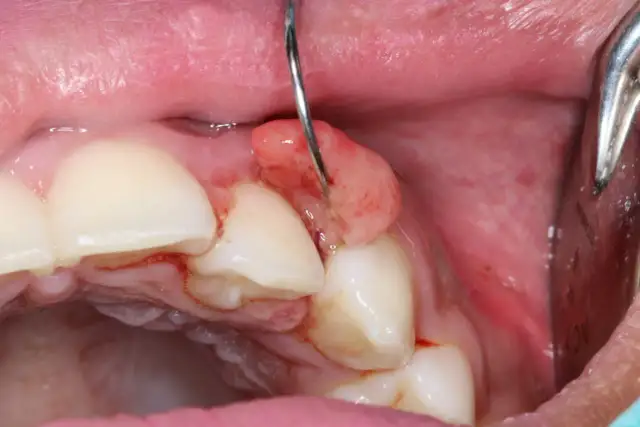

Wizualizacja zmian nowotworowych w jamie ustnej jest kluczowa dla diagnozy raka dziąseł. Zdjęcia raka dziąseł mogą ujawniać istotne cechy, które pomagają lekarzom w ocenie stanu pacjenta. Obrazy te mogą być używane do porównania z innymi przypadkami, co ułatwia postawienie diagnozy. Dzięki zdjęciom można również ocenić postęp choroby oraz skuteczność zastosowanego leczenia.

Ważne jest, aby zwracać uwagę na szczegóły na zdjęciach. Kluczowe cechy obejmują rozmiar, kształt oraz kolor zmian. Na przykład, guzki mogą być twarde i zgrubiałe, a owrzodzenia mogą mieć nierówne brzegi. Zrozumienie tych cech jest niezbędne dla właściwej diagnozy i leczenia. Warto również pamiętać, że zdjęcia powinny pochodzić z wiarygodnych źródeł medycznych, aby zapewnić ich dokładność.

Przykłady zdjęć zmian nowotworowych na dziąsłach

W celu lepszego zrozumienia, jak wygląda rak dziąseł, warto zapoznać się z przykładami zdjęć zmian nowotworowych. Takie obrazy mogą ukazywać różnorodne formy zmian, od guzków po owrzodzenia, które są kluczowe dla wczesnej diagnozy. Na przykład, zdjęcia mogą przedstawiać twarde guzki w okolicy zębów trzonowych oraz owrzodzenia, które nie goją się przez dłuższy czas. Obserwacja tych zmian jest istotna, ponieważ mogą one wskazywać na zaawansowany stan choroby.

Jak interpretować zdjęcia raka dziąseł – kluczowe cechy

Interpretacja zdjęć zmian nowotworowych na dziąsłach wymaga uwagi na kluczowe cechy, które mogą wskazywać na obecność raka. Przede wszystkim, należy zwrócić uwagę na kształt zmian; guzki powinny być twarde i zgrubiałe, a owrzodzenia mogą mieć nierówne brzegi. Kolor zmian również ma znaczenie – zmiany mogą być białe, czerwone lub ciemnoczerwone, co może sugerować różne stany patologiczne. Ponadto, ważne jest, aby ocenić, czy zmiany są statyczne czy też się rozwijają, co również wpływa na diagnozę.

W przypadku zdjęć, które wykazują cechy zapalne, takie jak obrzęk lub zaczerwienienie, również powinny być brane pod uwagę. Dokładna analiza tych cech jest kluczowa dla postawienia właściwej diagnozy i podjęcia odpowiednich działań terapeutycznych. Warto, aby pacjenci konsultowali się z lekarzem w celu omówienia wszelkich niepokojących zmian, które zauważą na zdjęciach.